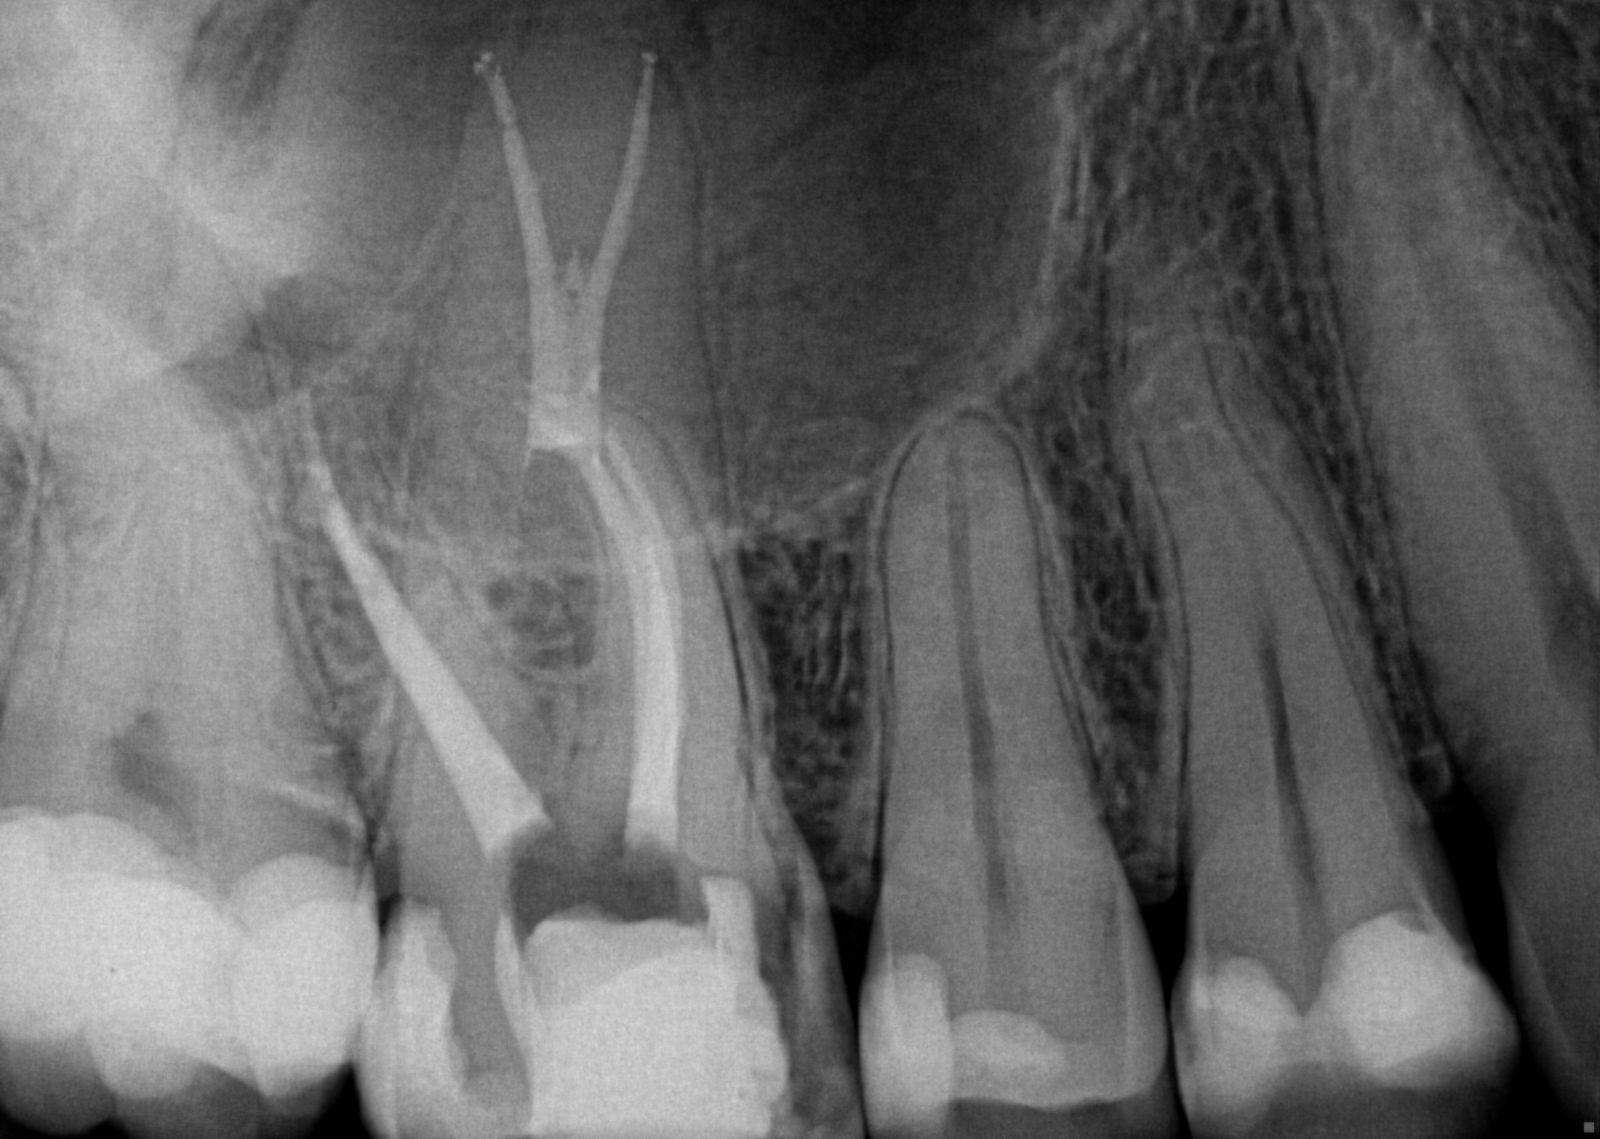

Digital radiograph illustrating the reference endodontic file (a) and Endodontic In X Ray Imaging technology aids in the diagnosis of endodontic pathosis and canal morphology, assessing root and alveolar. Dental radiography allows for the. Describe the importance of radiographs in endodontic diagnosis, treatment, and postoperative evaluation. It demonstrated to be an excellent asset for endodontics because of the number of radiographs indicated before, during, and after Digital radiography is firmly established as an. Endodontic In X Ray.